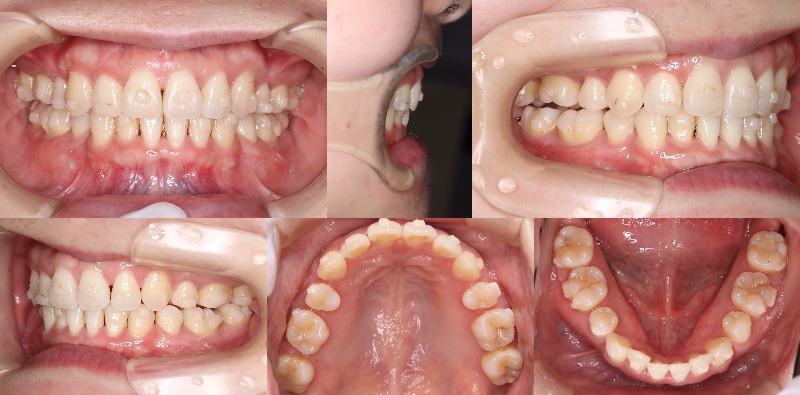

smartee症例のアタッチメント脱離についてご相談させてください。

Cくん 男児

現在9ステージ目使用中です。

他の症例では問題なく経過しておりますが、

本症例に限っては、

装着から約2週間で毎回ほとんどのアタッチメントが脱離している状態です。このままでは計画通りの進行が難しいと感じております。

現在の装着手順は以下の通りです。

・歯面研磨:メルサージュ使用

・エッチング(EE)、ボンディング(EB)実施

・アタッチメントテンプレート使用

・フローレジン:オムニクロマ使用なお、現在は9ステージ目まで進んでおりますが、

進捗への影響も懸念されるため、

再スキャンが必要な場合はご指示いただけますと幸いです。つきましては、以下についてご教示いただけますでしょうか。

① 小児症例特有の脱離リスク(エナメル質の性状など)の影響について

② 材料選択(オムニクロマ)の適否

③ 小児における有効な接着手技のポイント

④ 咬合干渉や生活習慣(咬み癖など)の影響の考え方本症例のみで起きている現象のため、

個別要因が強いのではないかと考えております。口腔内写真

〇アタッチメント取れなかった

×アタッチメントダツリお忙しいところ恐縮ですが、

ご教示のほどよろしくお願いいたします。 -